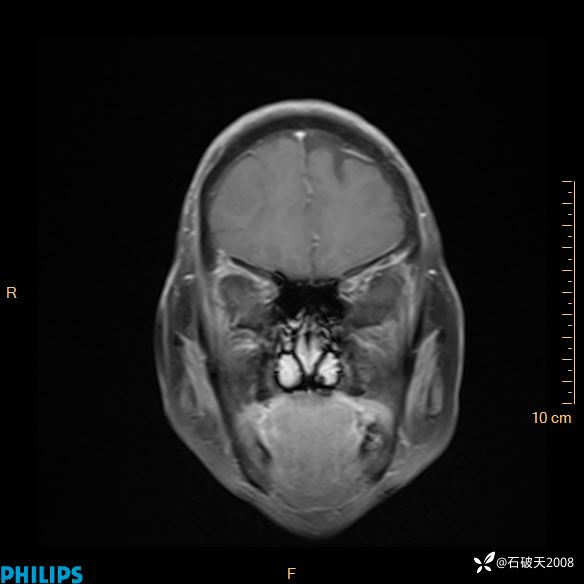

2024.2.21MR

增强冠状位